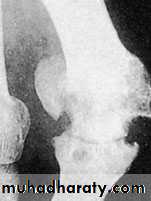

X-ray:

Taken with the patient standing to show the degree of metatarsal and hallux angulations.Also it shows the state of the joint being normal, arthritic or subluxated.

Show signs of osteoarthritis with narrowing of the joint space and sclerosis with big osteophytes.Treatment: